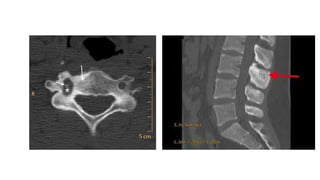

Los osteomas osteoides a menudo son difíciles de detectar en radiografías debido a su pequeño tamaño,

apariencia radiolúcida y ubicación del elemento posterior. Tomografía computarizada (TC) demuestra un nido

radiotransparente con o sin intranidal calcificación y engrosamiento cortical circundante y esclerosis con gran

éxito.

Más del 50% de los nodos son parcialmente calcificado, el 20% está completamente calcificado y el 30% no

muestra calcificaciones.